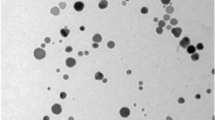

DNA fragmentation

As presented in Fig. 3, a smear ladder formation on agarose gel electrophoresis, revealing random DNA fragmentation, was observed in the kidney tissue of maneb-treated mice. Zn co-treatment decreased the smear formation. DNA damage was not detected in negative and positive control groups.

Regarding DNA damage of kidney tissue triggered by maneb exposure, our study demonstrated a higher intensity of DNA laddering on agarose gel electrophoresis as compared to the controls, which might be attributed to oxidative stress induced by this fungicide. Our previous study confirmed the genotoxic effect of maneb in the liver (2019). According to Bertini et al. (2000), ethylene thiourea the main metabolite of maneb, has been proven to have genotoxic effects in Wistar rats. In the present study, Zn co-administration led to a reduced DNA fragmentation induced by maneb. Thereby, Zn could protect DNA and other important molecules from oxidation, improving consequently kidney function. In fact, it exhibited DNA protection, attenuated lipid peroxidation, and decreased free radicals production indicating its strong antioxidant power. Our results were in accordance with other studies (Varghese et al. 2009), showing that Zn reduces the oxidative DNA damage in the kidney of rats exposed to indomethacin, a non-steroidal anti-inflammatory drug.